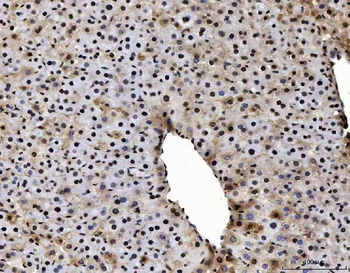

10 μg, 100 μgAnti-Alpha Actinin 4/ACTN4 Antibody [orb371708]

FC, ICC, IF, IHC, WB

Human, Mouse, Rat

Rabbit

Polyclonal

Unconjugated